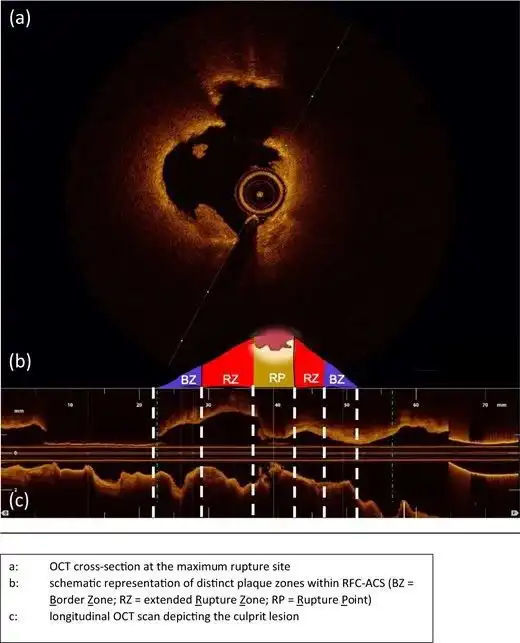

比较神秘一点的头像秘密 描述: 比较神秘一点的头像秘密 创立日期: 2025-05-15 00:07:34 图片数量: 0 pics 浏览量: 每个星座都有自己的阴暗面,这4个星座格外会隐藏,你知道吗 朱立鹏哇靠一则小小的整形广告,竟然隐藏如此多秘密 郭富城秘密访客票房破1亿,第一波影评出炉细节是重点 吃鸡游戏碰到机器人,倍镜下的脸很怪异,网友光子的秘密暴露了 十二星座,3大星座近期运势,字面解析 风水一点也不神秘 能用到版本末的9职业最强卡组,都在这里了 斑块破裂的另一个秘密 qq好友的秘密是自己好友发的吗 同样是姑娘,差距为什么这么大 lol最神秘的传送点,皇子旗子只排第四,最后一个传送他无敌 千万别点开这是互联网人的一个惊天大秘密 造福塌鼻梁,撑起颜值顶峰的妆容全靠它 一夜暴富不是梦山谷地图那些秘密资源点 类别: 2025头像大全